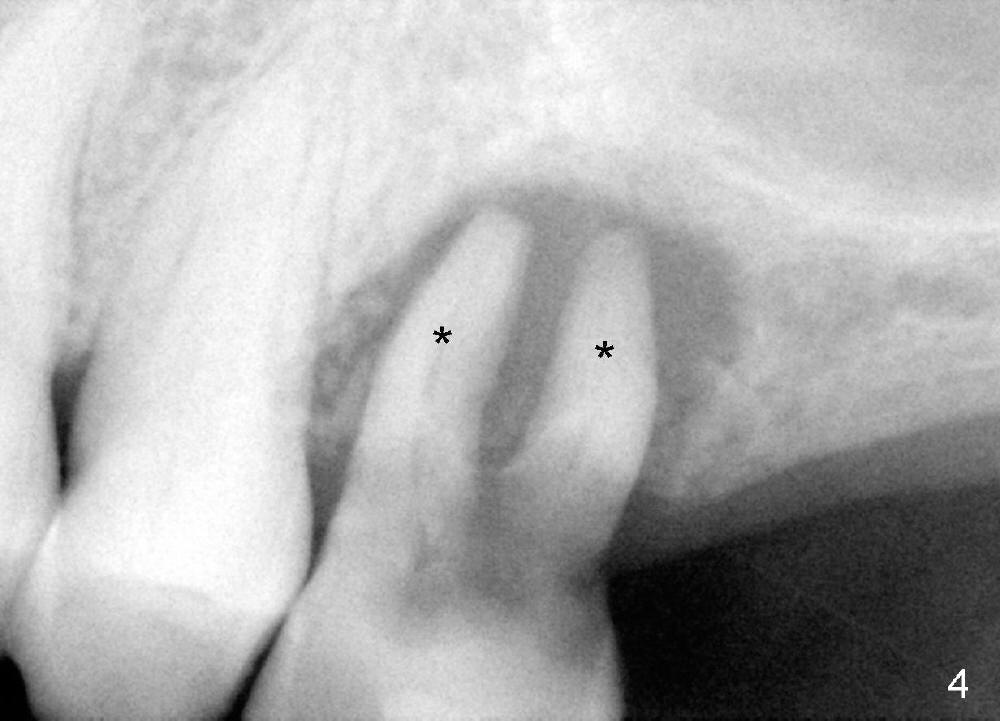

A 24-year-old man has poor dentition. The tooth #14 is beyond salvageable (Fig.1). The extraction socket is large (Fig.2). Dry socket develops 6 days post extraction without socket preservation (Fig.3).